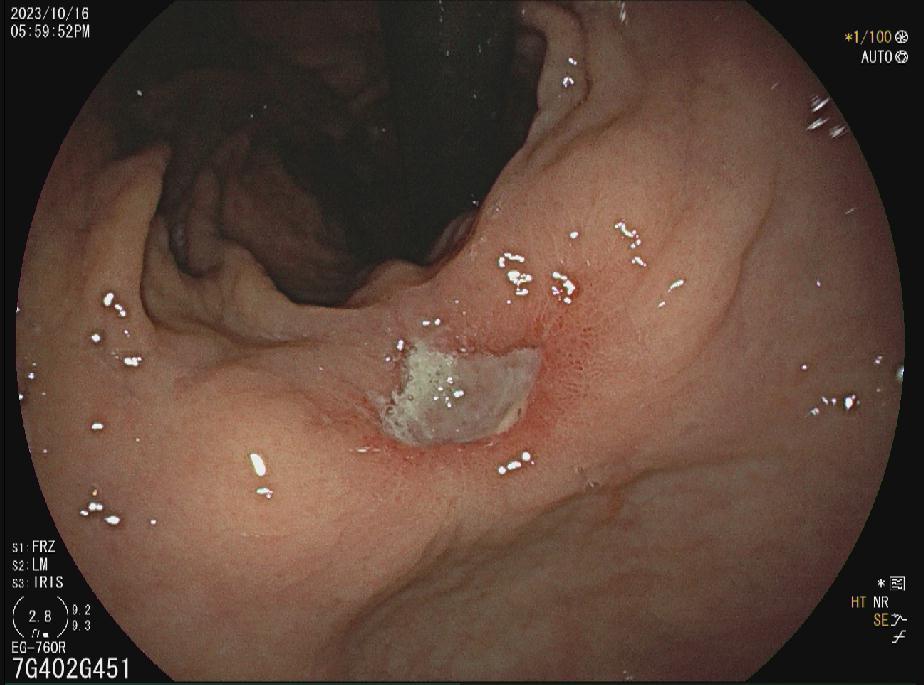

十二指肠球部溃疡

胃窦多发溃疡

胃窦溃疡

胃角溃疡

HPA感染鸡皮样胃炎

胃癌